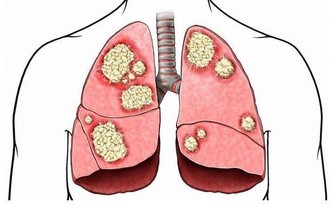

近些年來,關於腸道菌群功能的研究日新月異,我們終於了解到,這些寄宿在我們腸道中的小東西不僅僅是食物殘渣的消化者,更能夠影響我們身體功能的方方面面——已有研究發現,腸道菌群能影響機體的免疫系統,而腸道菌群失衡還可能會導致肥胖、糖尿病等疾病,更有新研究發現,腸道菌群與血壓水平也有關係。

維持血壓精妙平衡的重要作用不言而喻:血壓水平過低可能會導致生物體失去意識,而血壓偏高時給血管和心臟帶來的壓力則是致命的。但血壓維穩的難點在於,血液中的營養物質和化學信號輕而易舉就能打破平衡,所以控制血壓的機制也必須是動態的、能夠響應機體變化的。有研究人員發現,維持血壓的動態平衡也離不開腸道菌群的幫助。